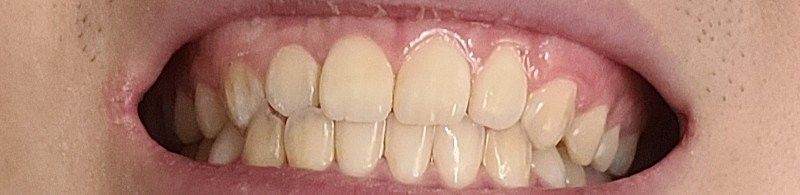

앞니 아랫니 포개긴하는데 덜 포개는 느낌이 들어요

겨우 포개는 느낌적인 느낌?

원래좀더 윗치아들이 앞으로 조금더 나와야하지 않나 그렇게 생각합니다

윗치아들이 덜 나온건지 아랫치아들이 많이 나온건지 모르겠어요

윗니가 앞으로 나오는 정도는 사람마다 다릅니다. 지금 사진상으로 보아 윗니가 앞으로 나온 양이 조금 적어 보이나

정상 범위입니다. 다만 오른쪽 작은 앞니(측절치)는 아랫니가 앞으로 나온 반대교합 입니다.